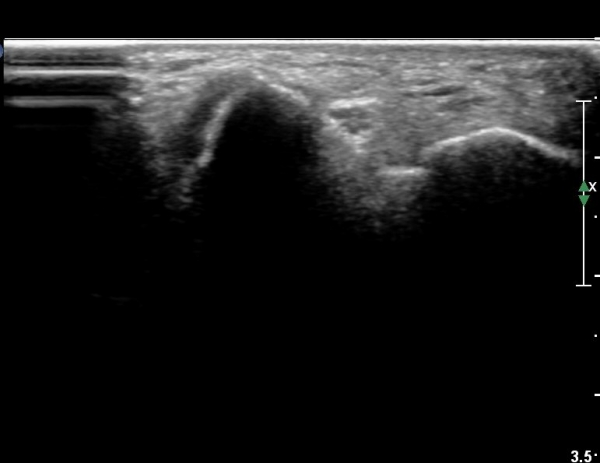

³²ÀÚ/46¼¼